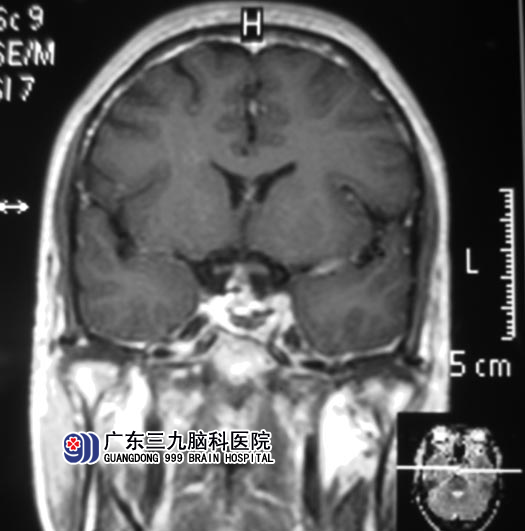

6月25日,鲁明主任主刀,术前制定导航计划,术中再次导航定位肿瘤,显微镜下见肿瘤呈黄白色,质中,在镜下予肿瘤全切,术中未损伤视神经,修补颅底,手术顺利结束。术后未出现尿崩、离子紊乱、脑脊液漏等并发症,双眼视力较术前好转,康复出院。术后病理:垂体腺瘤。

▲手术后